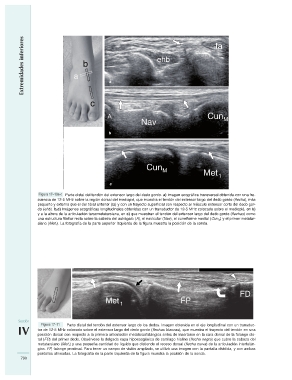

Figura 17–10a-c Parte distal del tendón del extensor largo del dedo gordo. a) Imagen ecográfica transversal obtenida con una fre-

cuencia de 12-5 MHz sobre la región dorsal del mediopié, que muestra el tendón del extensor largo del dedo gordo (flecha), más

pequeño y externo que el del tibial anterior (ta) y con un trayecto superficial con respecto al músculo extensor corto del dedo gor-

do (ehb). b,c) Imágenes ecográficas longitudinales obtenidas con un transductor de 12-5 MHz colocado sobre el mediopié, en b)

y a la altura de la articulación tarsometatarsiana, en c) que muestran el tendón del extensor largo del dedo gordo (flechas) como

una estructura fibrilar recta sobre la cabeza del astrágalo (A), el navicular (Nav), el cuneiforme medial (CunM) y el primer metatar-

siano (Met1). La fotografía de la parte superior izquierda de la figura muestra la posición de la sonda.

Sección Figura 17–11 Parte distal del tendón del extensor largo de los dedos. Imagen obtenida en el eje longitudinal con un transduc-

tor de 12-5 MHz colocado sobre el extensor largo del dedo gordo (flechas blancas), que muestra el trayecto del tendón en una

IV posición dorsal con respecto a la primera articulación metatarsofalángica antes de insertarse en la cara dorsal de la falange dis-

tal (FD) del primer dedo. Obsérvese la delgada capa hipoecogénica de cartílago hialino (flecha negra) que cubre la cabeza del

790 metatarsiano (Met1) y una pequeña cantidad de líquido que distiende el receso dorsal (flecha curva) de la articulación interfalán-

gica. FP, falange proximal. Para tener un campo de visión ampliado, se utilizó una imagen con la pantalla dividida, y con ambas

pantallas alineadas. La fotografía de la parte izquierda de la figura muestra la posición de la sonda.